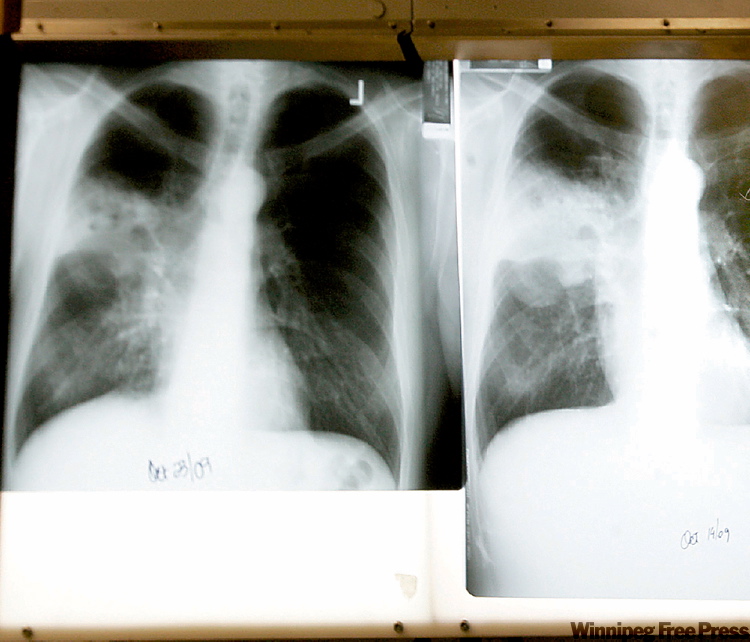

TB cases on rise in Manitoba

The latest provincial disease statistics reveal Manitoba recorded 156 TB cases in 2009 — the highest number recorded in a single year since the late 1970s. In the past four years TB cases have jumped by 50 per cent, leaving Manitoba with higher rates of the disease than any other province.